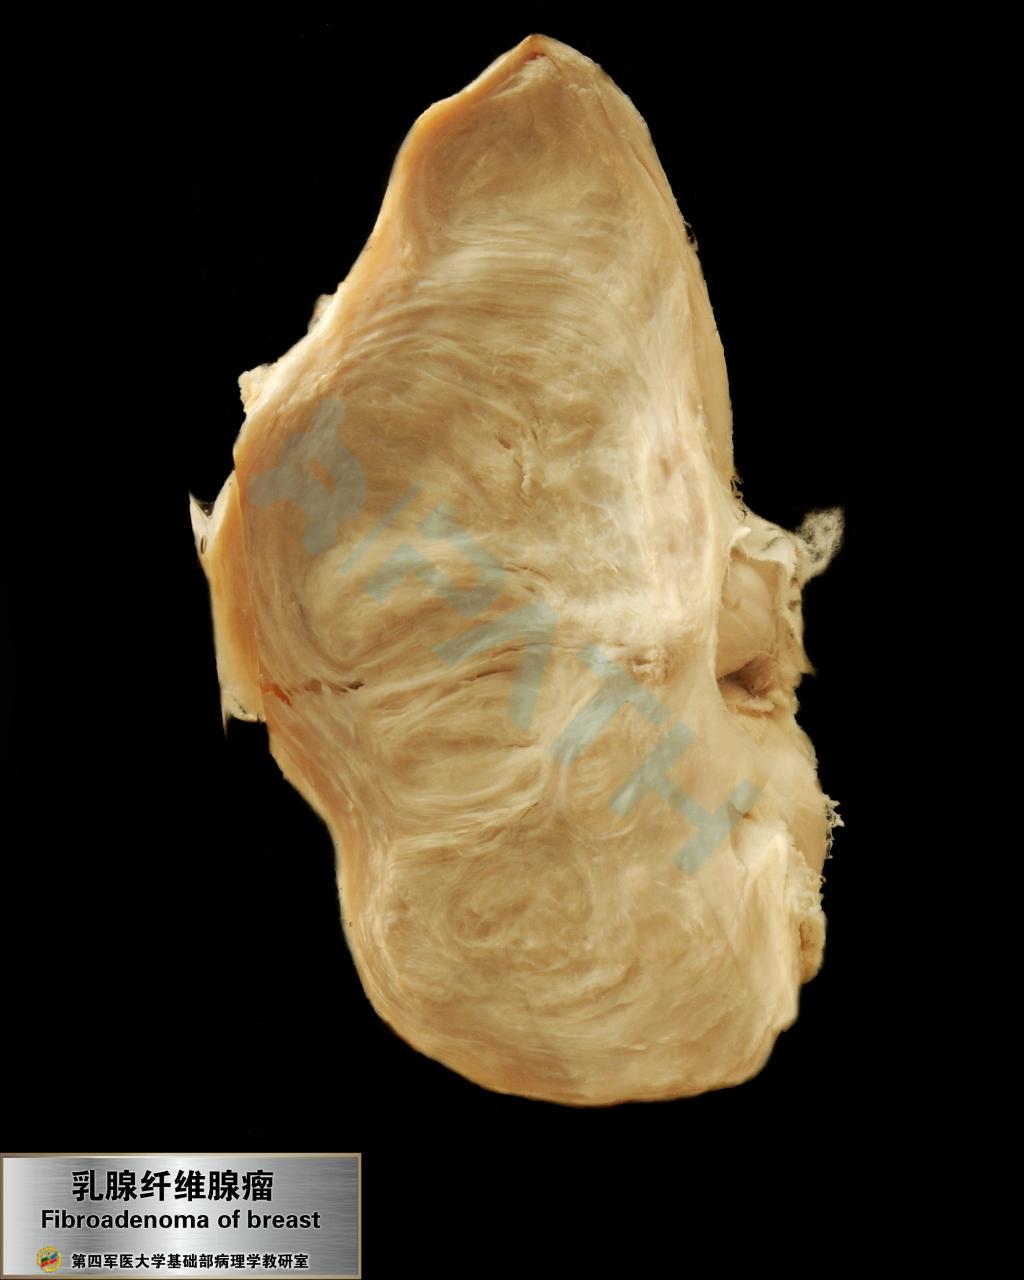

乳腺纤维腺瘤